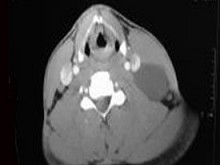

八歲患者,男性,因頸前正中包塊6年入院,查體:頸前正中舌骨下方可觸及一圓形包塊,囊性,無壓痛,隨吞咽上下活動。

8.患者腫塊圖像及影像學檢查結果見下圖,本患者應考慮為  (    )

9.如果考慮為你所選的上述疾病,手術前應該完善下面那個檢查  (    )

正確答案:8.A;9.A